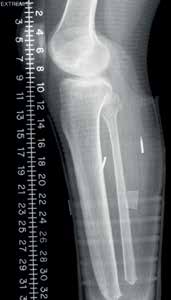

Zwei Beinamputierte wurden für eine IMES-Studie ausgewählt: ein Oberschenkelamputierter (TF = transfemoral) und ein Unterschenkelamputierter (TT = transtibial). Bei beiden Amputierten handelte es sich um erfahrene Anwender mit dem Aktivitätsgrad K3. Feine Drahtelektroden wurden verwendet, um zu überprüfen, dass von jedem Muskel bei einer willkürlich ausgelösten Kontraktion ein ausreichendes myoelektrisches Signal erfasst werden konnte. Zwei IMES-Sensoren wurden anschließend bei beiden Anwendern implantiert, beim oberschenkelamputierten Probanden in den Musculus biceps femoris und den Musculus vastus lateralis und beim unterschenkelamputierten Probanden in den Musculus tibialis anterior und den Musculus gastrocnemius. Jeder Eingriff dauerte etwa 30 Minuten und wurde unter lokaler Anästhesie und leichter Sedierung durchgeführt (Abb. 1). Beide Probanden wurden darum gebeten, bis zwei Wochen nach der Operation Unterarmgehstützen anstelle ihrer Prothesen zu verwenden, und es wurde ihnen eine vierwöchige Rehabilitationszeit gewährt, bevor mit den IMES-Tests begonnen wurde.

Jeder Sensor hat einen Durchmesser von etwa 2,5 mm und eine Länge von 16 mm, wobei die kundenspezifische Elektronik in einem Keramikzylinder untergebracht ist. Jedes Zylinderende ist aus leitfähigem Metall hergestellt, das als Elektrode dient (Abb. 2). Nach der Implantation wurden Röntgenbilder aufgenommen, um zu bestätigen, dass das Implantat an der richtigen Stelle sitzt, entsprechend der beabsichtigten Platzierung des Schafts (Abb. 3). Nachdem die Sensoren in die verbleibenden Muskeln des Stumpfes implantiert wurden, kann der im Prothesenschaft untergebrachte Spiral-Empfänger dazu verwendet werden, drahtlos über ein magnetisches Feld Energie und Informationen an die IMES zu übermitteln und von diesen zu empfangen. Der Spiraldraht-Empfänger wird mittels eines Spulentreibers gesteuert, der das magnetische Feld reguliert. Die IMES-Steuerschnittstelle versorgt den IMES mit Energie, sorgt für die Programmierung, empfängt Daten vom IMES und ist mit dem Message Broker für das bionische Signal (BSMB = „bionic signal message broker“) verbunden, der das IMES-System und die Prothesen von Össur miteinander verbindet (Abb. 4). Die IMES sind aufgrund von Stabilitätsproblemen nur in der Lage, gefilterte, gleichgerichtete und integrierte Signale zu versenden, und die Abtastrate des Sensors betrug 236 Abtastwerte pro Sekunde.